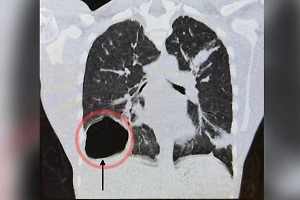

Пациент с дуоденальной кистозной дистрофией кишечника. Фото © Министерство здравоохранения Московской области

Пациента с дуоденальной кистозной дистрофией кишечника требовалось срочно прооперировать. Врачи удалили поражённую часть 12-перстной кишки и часть желудка, чтобы восстановить проходимости верхнего отдела желудочно-кишечного тракта.